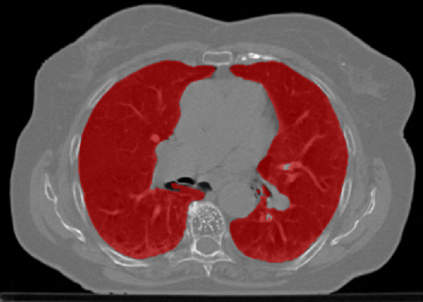

The COVID-19 pandemic has had a considerable impact on day-to-day life. Tackling the disease by providing the necessary resources to the affected is of paramount importance. However, estimation of the required resources is not a trivial task given the number of factors which determine the requirement. This issue can be addressed by predicting the probability that an infected patient requires Intensive Care Unit (ICU) support and the importance of each of the factors that influence it. Moreover, to assist the doctors in determining the patients at high risk of fatality, the probability of death is also calculated. For determining both the patient outcomes (ICU admission and death), a novel methodology is proposed by combining multi-modal features, extracted from Computed Tomography (CT) scans and Electronic Health Record (EHR) data. Deep learning models are leveraged to extract quantitative features from CT scans. These features combined with those directly read from the EHR database are fed into machine learning models to eventually output the probabilities of patient outcomes. This work demonstrates both the ability to apply a broad set of deep learning methods for general quantification of Chest CT scans and the ability to link these quantitative metrics to patient outcomes. The effectiveness of the proposed method is shown by testing it on an internally curated dataset, achieving a mean area under Receiver operating characteristic curve (AUC) of 0.77 on ICU admission prediction and a mean AUC of 0.73 on death prediction using the best performing classifiers.